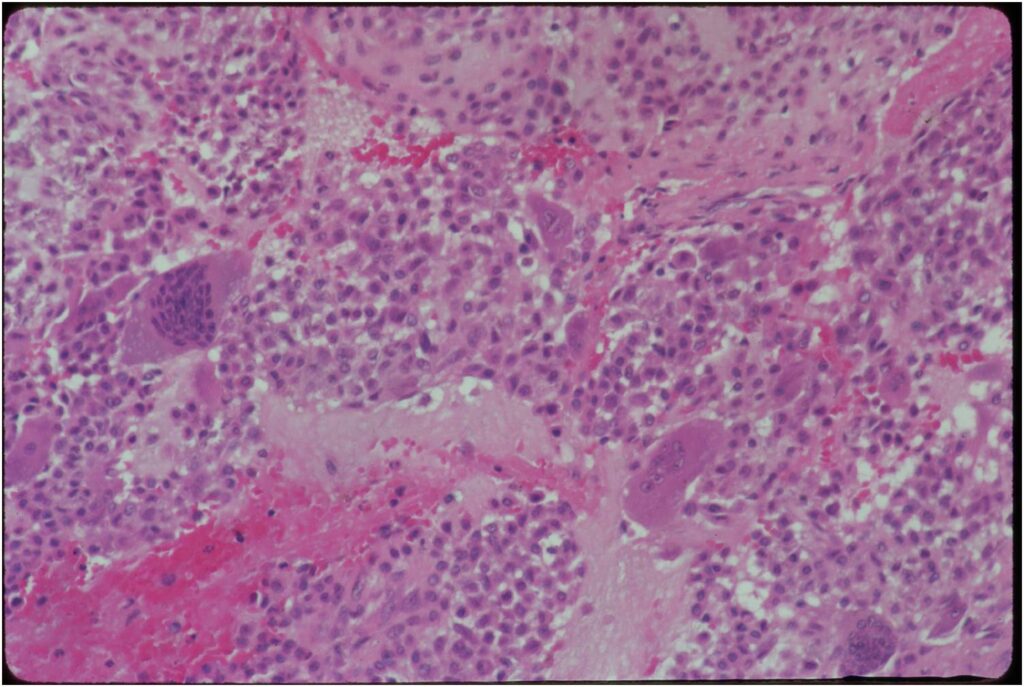

Gross Pathology

- Grossly variable appearance

- Grey/yellow/brown and gritty if has interspersed calcifications

- Interspersed red areas from hemorrhagic necrosis

- May be blue-grey areas from the chondroid matrix

- Rim of sclerotic bone is visible in totally resected specimens

- Lesion may be fully cystic with solid foci of tumor tissue at periphery

- May undergo aneurysmal bone cyst change (ABC change)

Microscopic Pathology

- Variable appearance depending on percentage of cells, necrosis, cartilage matrix formation and ABC change

- Chondroid matrix in up to 15% of tumor

- ABC component 5-15% of tumors

- The tumor is composed of chondroblasts that have a distinct, thick cell membrane. The thick cell membrane gives it a “Chicken Wire Fence Appearance,” especially when the cell membranes are calcified